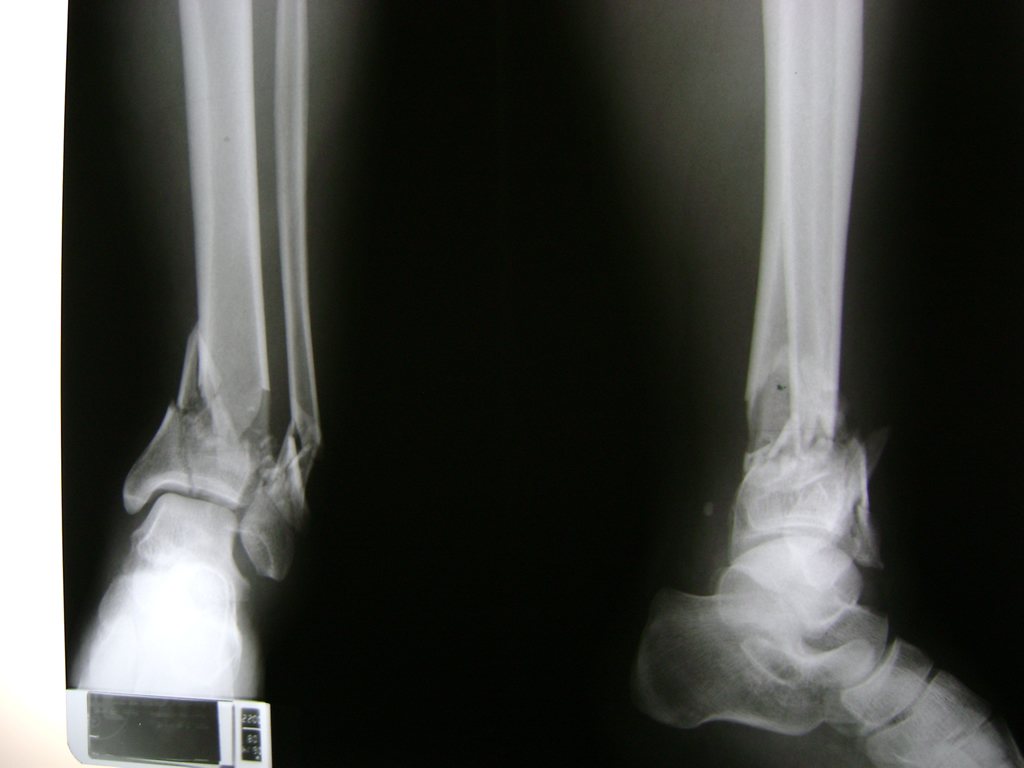

Una fractura de tobillo es la rotura de uno o más de los huesos del tobillo. Estas fracturas pueden ser:

- Parciales (el hueso está sólo parcialmente fisurado, no del todo).

- Completas (el hueso está perforado y está en 2 partes).

- Producirse en uno o ambos lados del tobillo.

Algunas fracturas de tobillo pueden requerir cirugía si:

- Los extremos de los huesos están desalineados entre sí (desplazados).